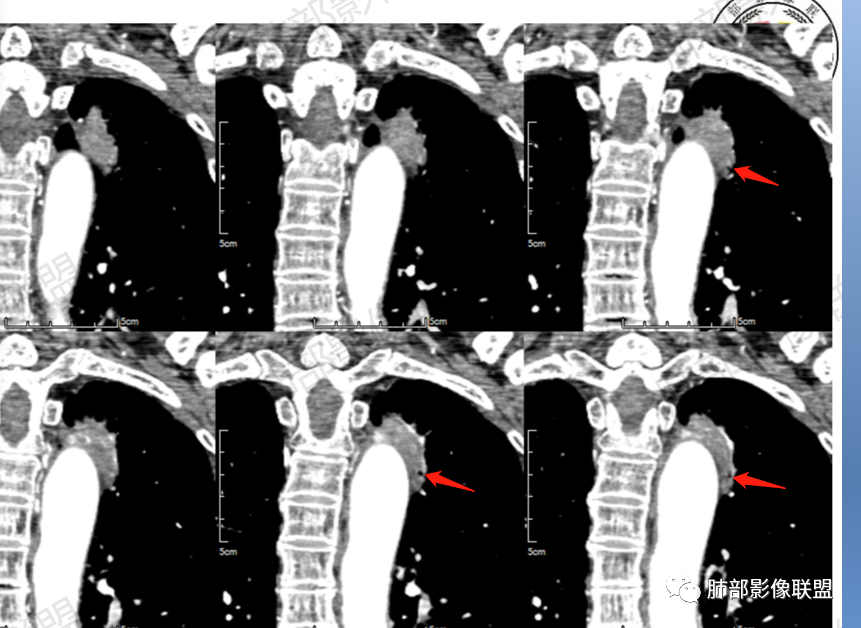

尘缘:病灶沿主动脉匍匐样生长,但整体明显膨隆,胸膜牵拉凹陷,局部有小喇叭口样改变。

尘缘:边界清楚的GGO。

4.冠矢状位病灶于弓上部偏后局限性“贝雷帽”状突起,提示病灶有局部膨隆特点,且病灶上份及后份饰以边缘较清楚磨玻璃影。

3.如前所述本例病灶定位于尖后段肺组织,冠矢状位病灶明显局限性膨隆感,如有老师分析时称“见较清楚磨玻璃边缘”——这应当是本例较重要诊断线索!

4.病灶显著强化是符合腺癌影像学特点的。

5.临床实践中,恶性肿瘤较少能够直接突破主动脉壁,尤其是腺癌。